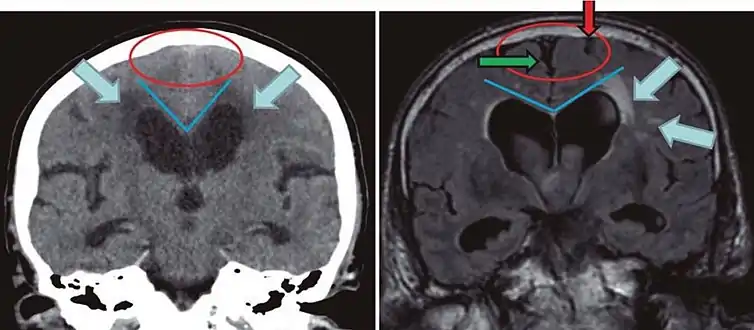

Cerebral atrophy can be hard to distinguish from hydrocephalus because both cerebral atrophy and hydrocephalus involve an increase in cerebrospinal fluid (CSF) volume. In cerebral atrophy, this increase in CSF volume comes as a result of the decrease in cortical volume. In hydrocephalus, the increase in volume happens due to the CSF itself.[20]

| Normal pressure hydrocephalus | Brain atrophy | |

|---|---|---|

| Preferable projection | Coronal plane at the level of the posterior commissure of the brain. | |

| Modality in this example | CT | MRI |

| CSF spaces over the convexity near the vertex (red ellipse | Narrowed convexity ("tight convexity") as well as medial cisterns | Widened vertex (red arrow) and medial cisterns (green arrow) |

| Callosal angle (blue V) | Acute angle | Obtuse angle |

| Most likely cause of leucoaraiosis (periventricular signal alterations, blue arrows |

Transependymal cerebrospinal fluid diapedesis | Vascular encephalopathy, in this case suggested by unilateral occurrence |